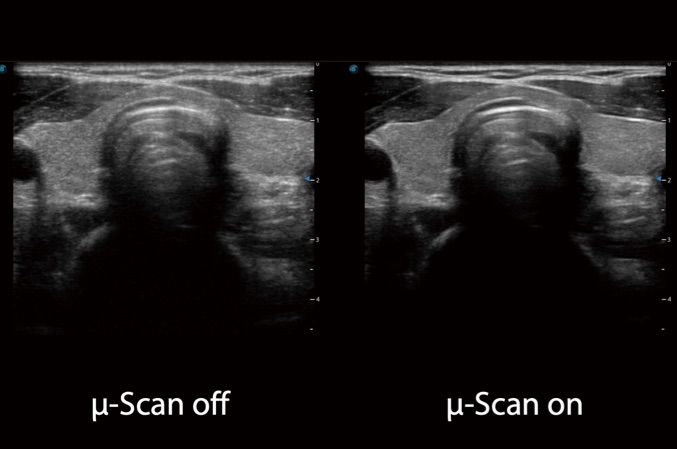

微米成像技術(shù)大大提高了器官和病變的可見(jiàn)性。高清對(duì)比度分辨率將抑制斑點(diǎn)噪聲,同時(shí)保持真實(shí)的組織結(jié)構(gòu)。